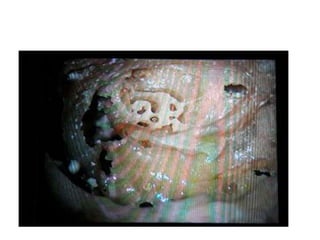

Probing in basal turn

Probe in basal turn opens into basal

turn cochleostomy in middle cranial

fossa

See all the turns of cochlea from

middle fossa